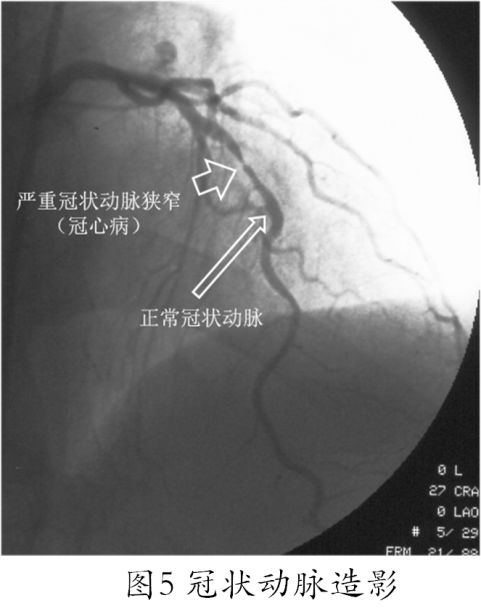

需要强调的是:对于绝大多数怀疑冠心病的患者来说经导管冠状动脉造影是目前诊断冠心病的“金标准”,它不仅可以直观而清晰地反映冠状动脉病变的几何学特征(图5)、也可间接地部分反映冠状动脉的功能状态(尤其是血流动力学特征)而且创伤小、副作用少、安全性较高,更重要的是冠状动脉造影结果也是对于确诊为冠心病的患者如何进行治疗决策的重要依据(冠状动脉造影可以明确冠状动脉病变的范围和程度,进而决定是单纯药物治疗即可、还是需要植入支架或接受冠状动脉搭桥手术)!无论在欧美等发达国家和地区还是在中国,冠状动脉造影这一成熟的诊断技术已经成为临床诊断冠心病、指导冠心病治疗策略、判断冠心病患者预后的一项常规技术,因此,如果医生认为有适应症,患者对于冠状动脉造影不必有太多顾虑。如果医生经过分析、判断认为患者有进行冠状动脉造影检查的明确指证而没有及时进行,则可能延误诊断和治疗。

冠状动脉造影的主要指征为:①已确诊为冠心病,药物治疗效果不佳,拟行介入性治疗或旁路移植手术;②心梗后再发心绞痛或运动试验阳性者;③有胸痛病史,但症状不典型,或无心绞痛、心肌梗死病史,但心电图有缺血性ST-T改变或病理性Q 波不能以其他原因解释者;④中老年患者心脏增大、心力衰竭、心律失常、疑有冠心病而无创性检查未能确诊者。⑤急性冠脉综合征拟行急诊PCI 者。冠心病患者了解上述指征也是很有必要的,当医生建议进行冠状动脉造影检查时,患者对上述指征有所了解后也更容易理解医生的建议,进而对是否接受冠状动脉造影检查做出合理的抉择。